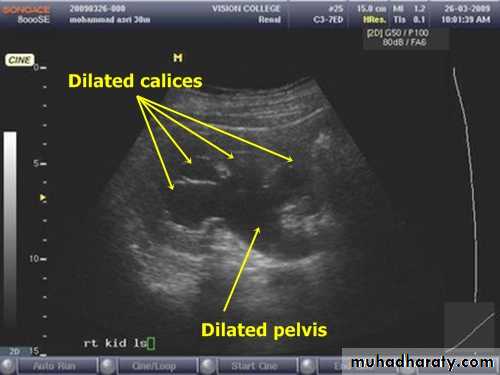

Early diagnosis of urinary tract obstruction is important because most cases can be corrected and a delay in therapy can lead to irreversible renal damage.Ultrasound Scan (USS): Simple and non-invasive. In most cases it can diagnose hydronephrosis and may detect its cause.

USS Showing hydronephrosis